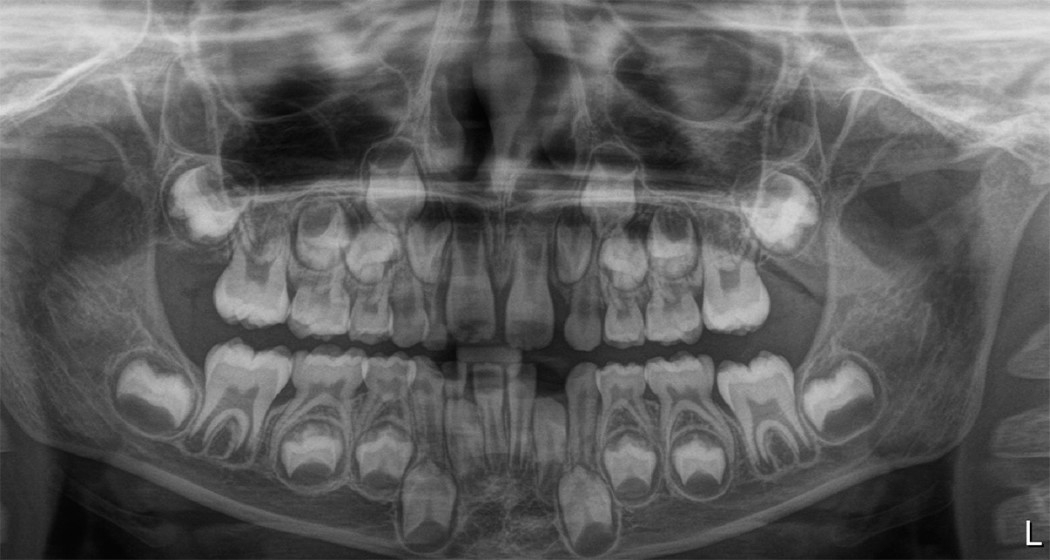

Röntgen görüntüsü, aşağıdaki bulgulara sahip bir hastayı (erkek, 6 yaşında) göstermektedir: 12 ve 22'de diş rotasyonu ile tıkanmış erüpsiyon.